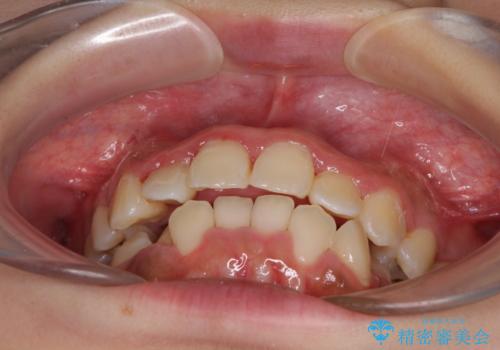

前後に重なった前歯 ワイヤー装置と急速拡大装置を併用したインビザライン矯正

- 前歯の著しい叢生とクロスバイトを気にして来院された患者様です。

叢生が強いため、一見すると抜歯矯正と判断したくなりますが、下顎臼歯が舌側に倒れていることから、上顎骨を側方拡大し、非抜歯矯正の可能性を検討することとしました。

急速拡大装置による上顎骨の側方拡大が思った以上にうまくいき、非抜歯での矯正が可能となりました。

内側に倒れていた下顎の臼歯は起き上がり、清掃性も大幅に改善されました。